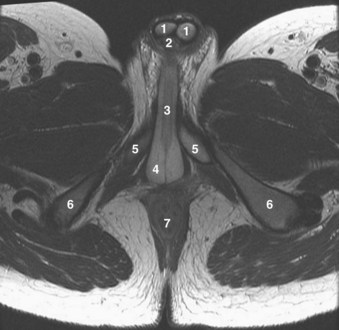

The urethra runs the length of the prostate and is usually closest to its anterior surface. It is lined by transitional epithelium, which may extend into the prostatic ducts. The urothelium is surrounded by an inner longitudinal and an outer circular layer of smooth muscle. A urethral crest projects inward from the posterior midline, runs the length of the prostatic urethra, and disappears at the striated sphincter (Fig. 2–35). To either side of this crest, a groove is formed (prostatic sinuses) into which all glandular elements drain (McNeal, 1972). At its midpoint, the urethra turns approximately 35 degrees anteriorly, but this angulation can vary from 0 to 90 degrees (see Figs. 2-27, 2-31, 2-36, and 2-37). This angle divides the prostatic urethra into proximal (preprostatic) and distal (prostatic) segments that are functionally and anatomically discrete (McNeal, 1972, 1988). In the proximal segment, the circular smooth muscle is thickened to form the involuntary internal urethral (preprostatic) sphincter described earlier. Small periurethral glands, lacking periglandular smooth muscle, extend between the fibers of the longitudinal smooth muscle to be enclosed by the preprostatic sphincter. Although these glands constitute less than 1% of the secretory elements of the prostate, they can contribute significantly to prostatic volume in older men as one of the sites of origin of benign prostatic hypertrophy.

Figure 2–38 Axial T2-weighted magnetic resonance image of the male pelvis through the prostate gland and adjacent structures. 1, urinary bladder; 2, lateral lobes of prostate; 3, verumontanum; 4, striated urethral sphincter; 5, inferior pubic ramus; 6, corpus spongiosum in cross section; 7, external iliac artery.

The glandular elements of the prostate have been divided into discrete zones, distinguished by the location of their ducts in the urethra, by their differing pathologic lesions, and, in some cases, by their embryologic origin (see Fig. 2–36). These zones can be demonstrated clearly with transrectal ultrasonography (Fig 2–39). At the angle dividing the preprostatic and prostatic urethra, the ducts of the transition zone arise and pass beneath the preprostatic sphincter to travel on its lateral and posterior sides. Normally, the transition zone accounts for 5% to 10% of the glandular tissue of the prostate. A discrete fibromuscular band of tissue separates the transition zone from the remaining glandular compartments and may be visualized at transrectal ultrasonography of the prostate. The transition zone commonly gives rise to benign prostatic hypertrophy, which expands to compress the fibromuscular band into a surgical capsule seen at enucleation of an adenoma. It is estimated that 20% of adenocarcinomas of the prostate originate in this zone.

The ducts of the central zone arise circumferentially around the openings of the ejaculatory ducts. This zone constitutes 25% of the glandular tissue of the prostate and expands in a cone shape around the ejaculatory ducts to the base of the bladder. The glands are structurally and immunohistochemically distinct from the remaining prostatic glands (which branch directly from the urogenital sinus), which has led to the suggestion that they are of wolffian origin (McNeal, 1988). In keeping with this suggestion, only 1% to 5% of adenocarcinomas arise in the central zone, although it may be infiltrated by cancers from adjacent zones.

The peripheral zone makes up the bulk of the prostatic glandular tissue (70%) and covers the posterior and lateral aspects of the gland. Its ducts drain into the prostatic sinus along the entire length of the (postsphincteric) prostatic urethra. Seventy percent of prostatic cancers arise in this zone, and it is the zone most commonly affected by chronic prostatitis.